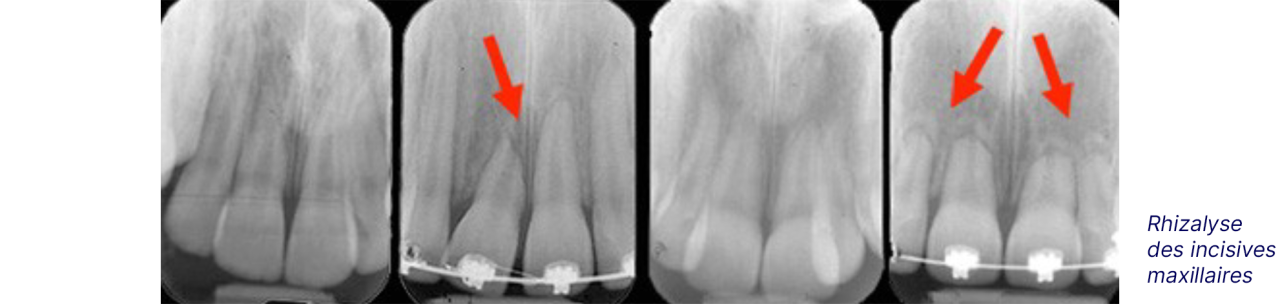

La résorption radiculaire / Rhizalyse

Les racines de certaines dents peuvent raccourcir ou « s’user » durant un traitement d’orthodontie. C’est ce que nous appelons la résorption des racines, résorption radiculaire ou rhizalyse.

Cependant ce phénomène de résorption est anormal sur les dents permanentes et peut apparaitre avec ou sans traitement orthodontique. Certaines publications ont montré que ce processus peut légèrement affecter toutes les dents mais il est à peine perceptible et sans conséquence.

Une dent incluse en contact avec la racine d’une dent voisine, des déplacements dentaires trop rapides, une force appliquée trop importante, la succion du pouce associée à un traitement d’orthodontie peuvent être à l’origine d’une résorption radiculaire.

Ce phénomène est irréversible ; une racine plus courte ne « repoussera » pas. Une résorption très importante peut, dans les cas extrêmes et rare, causer la perte d’une dent.

Radiographie exposant le risque de rhizalyse. Radiographie qui montre le risque de rhizalyse.